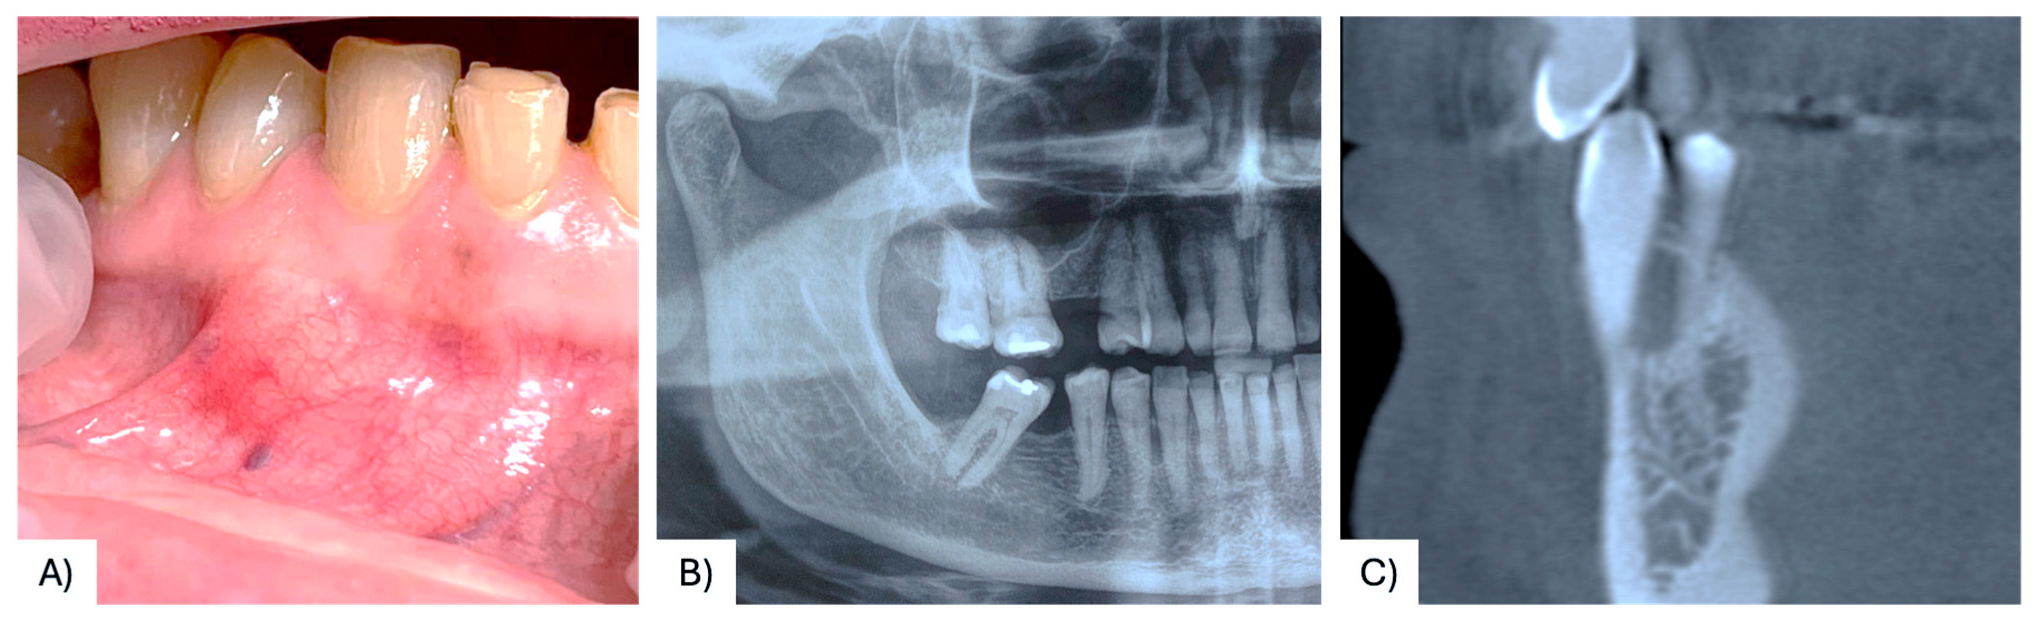

3.1. Case Presentation

| 37 | Present case | 68 F | Maxilla, between #4.3, #4.4 | Asymptomatic nodule | 15 mm | Radiolucency with a defined margin area | Alveolar bone resorption | Excisional biopsy, curettage | No recurrence at 6 months follow-up | 2025 |